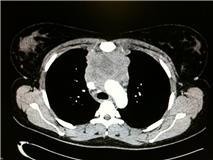

I had the CT Scan on the Monday evening as was ready to go home when my Consultant called me and Des in to the quiet room and then told me that I had a tumour in my chest.

The next few chemo sessions were similar to the first – I found that sleeping helped with the sickness (if I wasn’t awake I wasn’t being sick) and when I had another scan after my 4th chemo it showed that the tumour had shrunk by over 90% (which made it all feel worthwhile)!